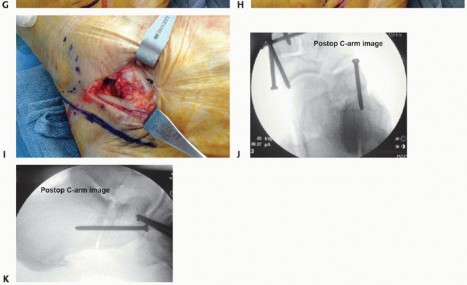

Elevate the extensor digitorum brevis muscle from the anterior process of the calcaneus to expose the superior corner of the calcaneocuboid joint and the sinus tarsi at the angle of Gissane (TECH FIG 1C).

Place two small Hohmann retractors, one in the sinus tarsi and the other plantar to the anterior calcaneus, after subperiosteal dissection to enhance exposure to the lateral column. - Osteotomy

Next, secure the graft with a single 3.5-mm fully threaded cortical screw from the anterosuperior corner of the calcaneocuboid joint across the graft into the proximal calcaneus (TECH FIG 3F-I).

- TECH FIG 3 • A. Marking the bone graft to the appropriate size. B. Bone graft wedge ready for implantation. C. Placing the bone graft into the osteotomy site. D. Tamping the bone graft into place. (continued)

Use AP and lateral fluoroscopic images to confirm position and restoration of the lateral column height, the talo-first metatarsal angle, and the talonavicular coverage angle (TECH FIG 3J,K).

- TECH FIG 3 • (continued) E. Impacted iliac crest wedge. F-I. Securing the graft with a single 3.5-mm screw from the anterosuperior corner of the calcaneocuboid joint through the graft and into the os calcis. J. AP C-arm image after procedure to confirm graft and screw position. K. Lateral C-arm image.